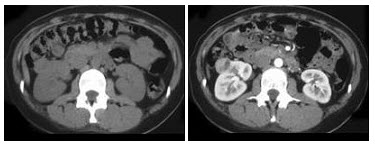

242、多项选择题

女,64岁,左侧腰部胀痛,行CT扫描,如图所示,下列说法正确的是()

A.左肾区可见一巨大的占位性病灶,境界较清楚,胰腺尾部受压向前推移

B.该病灶密度不均匀,其内可见脂肪密度影,且呈不均匀强化

C.考虑为左肾来源的血管平滑肌脂肪瘤

D.考虑为左侧肾上腺来源的髓样脂肪瘤

E.考虑为腹膜后来源的脂肪肉瘤